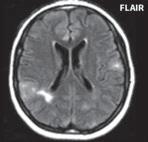

I 5 2 „Fyziologická“ ložiska zvýšeného signálu v T2W obrazu v bílé hmotě mozkové 187

Roztroušená skleróza (RS) 189